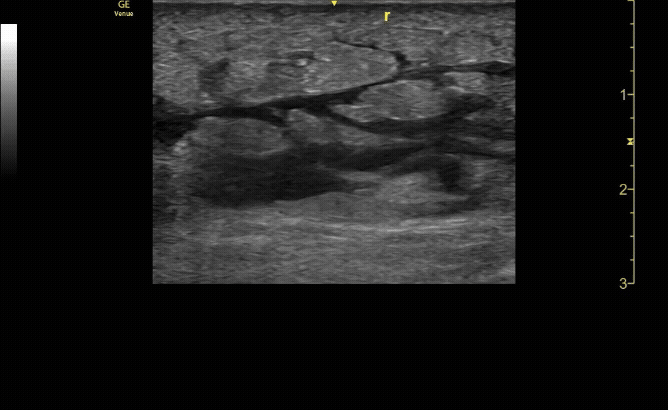

Extensor tenosynovitis in a patient following a cat bite.

Necrotizing fasciitis. Note air under the tendon.

c/o Adam Roussas, MD